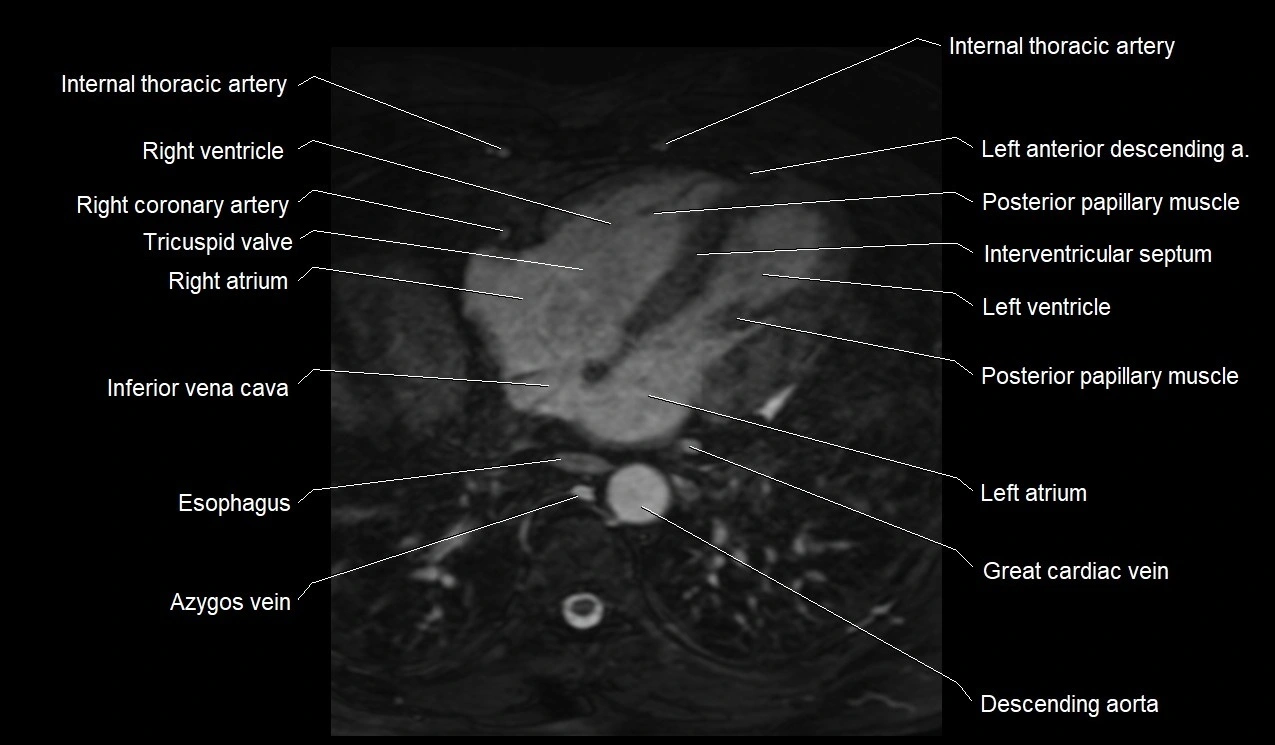

MRI image